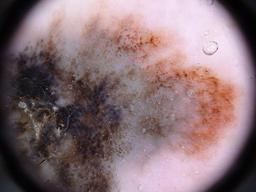

BRAAFF-Annotated Acral Lesions Dataset (BALD)

The BRAAFF-Annotated Acral Lesions Dataset (BALD): A curated set of dermatoscopic images of acral melanoma and nevi from various sources.

Müller C, Tschandl P, Rinner C, Kyrgidis A, Koga H, Moscarella E, Apalla Z, Di Stefani A, Kobayashi K, Lazaridou E, Longo C, Phan A, Saida T, Sotiriou E, Tanaka M, Thomas L, Zalaudek I, Argenziano G, Lallas A, Kittler H. The BRAAFF-Annotated Acral Lesions Dataset (BALD): A Curated Set of Dermatoscopic Images of Acral Melanoma and Nevi from Various Sources. J Invest Dermatol. 2025 Jan 17:S0022-202X(25)00021-1